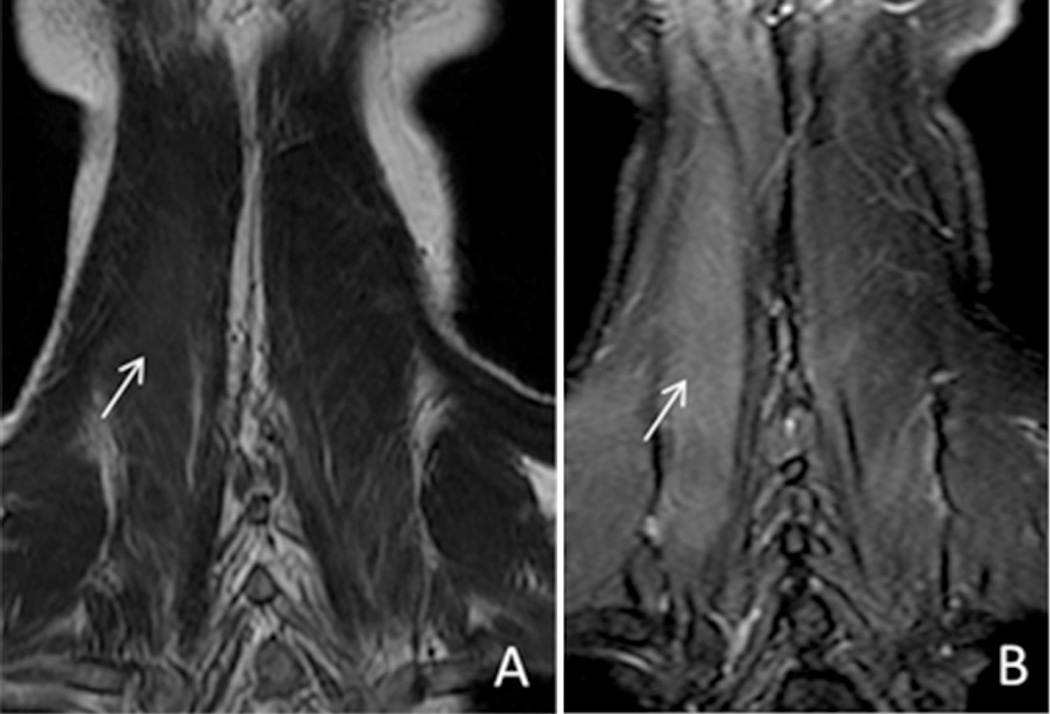

3.2. Inflammatory

The brachial and lumbosacral plexuses can be involved in the setting of infectious or inflammatory conditions. In these cases, the homogeneous fat suppression is indispensable to accurately diagnose subtle enhancement of the nerves and associated musculature. Fig. 3 clearly delineates the importance of fat suppression in diagnosing paraspinal muscle edema in an older patient who presented with severe anterocollis provoked by a previous C3–C6 radiofrequency rhizotomy (performed for chronic cervicalgia). Without homogeneous fat suppression, the subtle T2 hyperintensity (edema) and enhancement within the right paraspinal musculature may easily have been overlooked.

Fig. 3.

44 year old male with dropped head syndrome. Coronal T2 FSE (A) and T2 IDEAL (B) images demonstrate improved visualization of edema within the right paraspinal musculature with the use of a fat suppression technique (arrows).